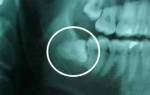

Во время сложного удаления зубов мудрости, хирург использует специальный инструмент, делает надрезы и затем зашивает раны. Эта операция часто выполняется на зубах, которые не могут правильно вырасти или находятся в горизонтальном положении. Врачу приходится удалить кость, чтобы достать зуб и его корни.

Операция проводится в хирургическом кабинете с использованием сильных обезболивающих средств. Все необходимые антисептические меры принимаются, чтобы обеспечить стерильность помещения. Через три дня рана зашивается рассасывающимися нитями, которые удаляются после заживления раны.

Фото после операции удаления зуба мудрости: